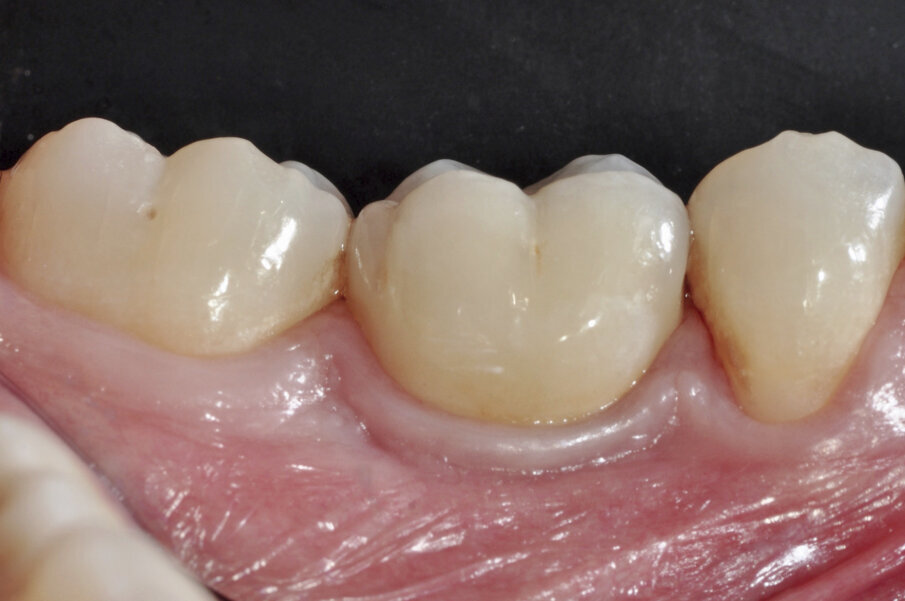

Fig. 18: After ten years, a perfect adjustment of soft tissue around

the restoration (buccal view) was observed, filling the space for the interproximal papillae and yielding a natural looking soft-tissue contour.